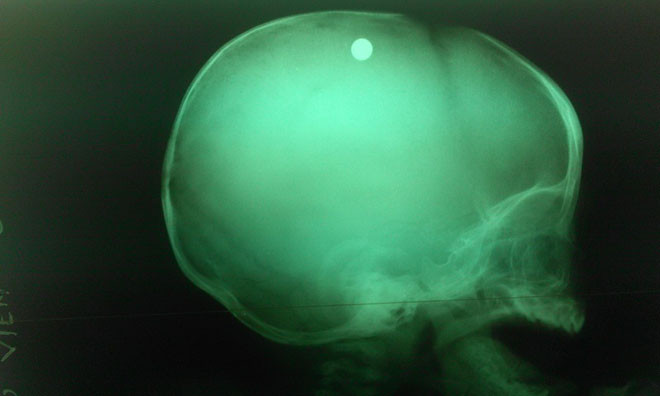

Viên đạn trong đầu bé trai 6 tuổi qua chụp X-quang- ảnh BV nhi đồng 2.

Các bác sĩ đã nhanh chóng xác định đây là trường hợp bị thương ở sọ não do hỏa khí gây ra, và cần phẫu thuật gấp vì kết quả chụp X- quang cho thấy viên đạn vẫn còn nằm trong sọ của bé.

Theo bác sĩ Đặng Xuân Vinh, viên đạn nằm trong nhu mô não, cách xương sọ 2cm.

“Đạn được bắn thẳng vào não. Đường đi của viên đạn này từ chẩm trái xuyên qua xương sọ vào nhu mô não, rồi lên đỉnh trái, cuối cùng chuyển hướng sang đỉnh phải đầu. Vì thế nhu mô não của bệnh nhi này bị tàn phá nặng, kèm xuất huyết não” - bác sĩ Vinh cho hay.